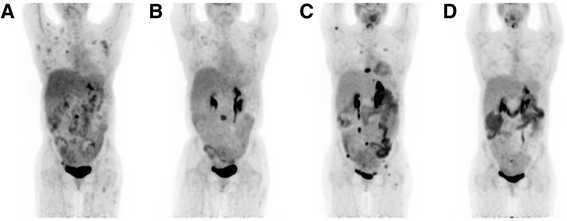

结果解读:治疗后患者发热、腹痛缓解,LDH从853 U/L(正常313~618 U/L)降至正常;2014年1月PET-CT显示淋巴结代谢接近完全缓解,但骨病变(左侧髂骨、L3椎体)仅部分缓解(图2b)。

方法细节:患者先接受L3椎体放疗(4000 cGy),追加4周期利妥昔单抗;2014年6月PET-CT显示骨病变进展(右侧肱骨等新发病灶,图2c),更换为维布妥昔单抗(1.8 mg/kg,每3周1次,共10周期),同时维持利妥昔单抗每2个月1次。

结果解读:2014年12月PET-CT显示所有病变代谢完全消失(完全缓解,图2d);治疗中仅出现中度神经病变(维布妥昔单抗常见不良反应),无严重感染。